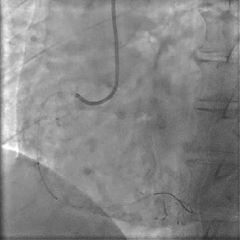

冠脉造影提示:左前降支近中段最重狭窄程度95%,钝缘支a最重狭窄80%,后侧支最重狭窄90%。于左前降支行介入治疗。

介入治疗过程:使用球囊预扩张后,成功于病变处植入2.25×20mm药物洗脱支架一枚,造影示支架定位良好,进行球囊后扩,术后IVUS检查示支架贴壁良好,支架边缘未见明显夹层血肿。

PCI术后即刻应用基于压力导丝的冠脉功能学全面评估解决方案(IMR/FFR等)进行全面评估,测得LAD IMR 46(+),FFR 0.87,提示存在CMD。心脏磁共振结果也提示存在微血管阻塞。

冠脉功能学全面评估:

◾ 首次入院

▶ LAD IMR 46(+),FFR 0.87。